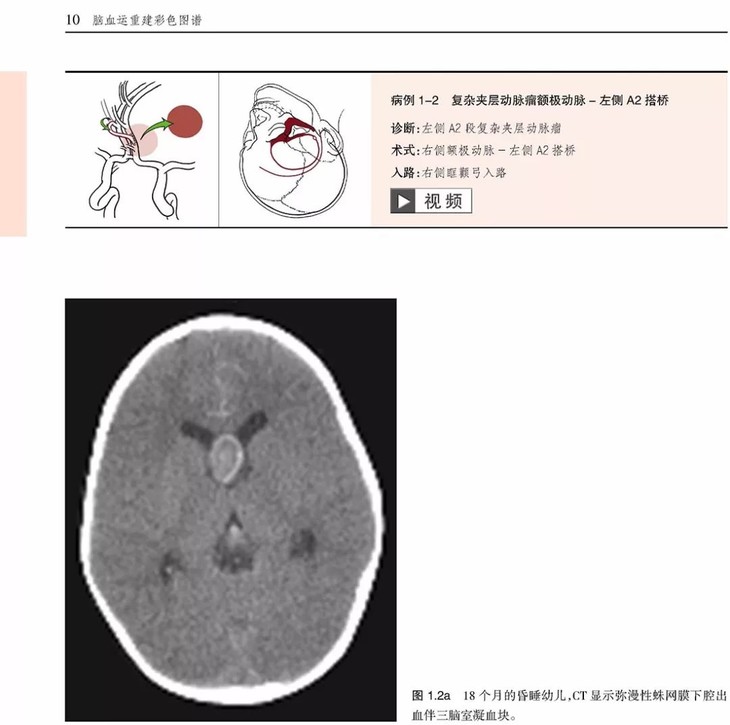

《脑血运重建彩色图谱:解剖、技巧及病例》主要介绍了脑血运重建手术的各种技巧和临床应用。这项技术是世界著名的亚利桑那州凤凰城巴罗神经病学研究所的外科医生首创的。每个步骤都以术中照片及精美的解剖图呈现,以帮助神经外科医生掌握复杂的显微外科解剖及微妙的外科技巧,从而用于治疗脑卒中潜在发作以及其他脑缺血疾病。

•描述了如何成功实施诸如烟雾病、血管内治疗后复发动脉瘤、巨大动脉瘤,以及椎动脉供血不足及重度狭窄的脑血运重建

•治疗临床病例的描述过程中展示了每种重建手术相关的血管解剖